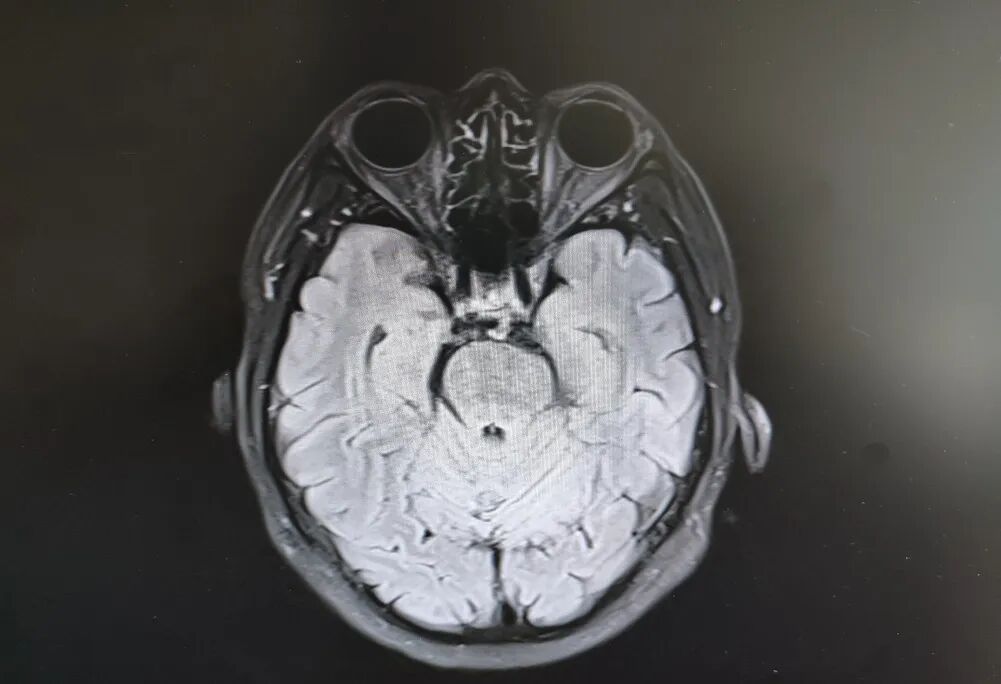

患者頭部磁共振影像

就在看似陷入僵局時,關鍵的血液檢查結果出來了——RPR陽性!這個結果像一盞明燈,指明了方向。原來,導致大爺眼病的幕后黑手,竟是由蒼白密螺旋體(引起梅毒的病原體)感染引起的神經損害。經過針對性治療,十幾天后,大爺的病情逐漸好轉,眼皮能抬起來了,重影消失了,眼球轉動也靈活了!